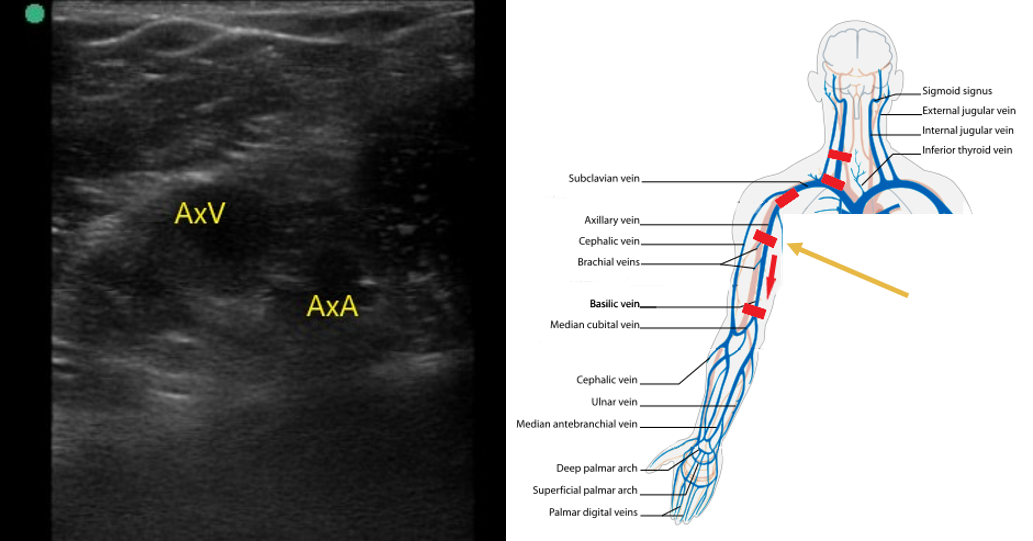

- Follow the axillary vein as it traverses into the proximal arm and compress along the way (Fig. 6).

- Figure 6. Axillary artery (AxA) and axillary vein (AxV) in the proximal upper arm.